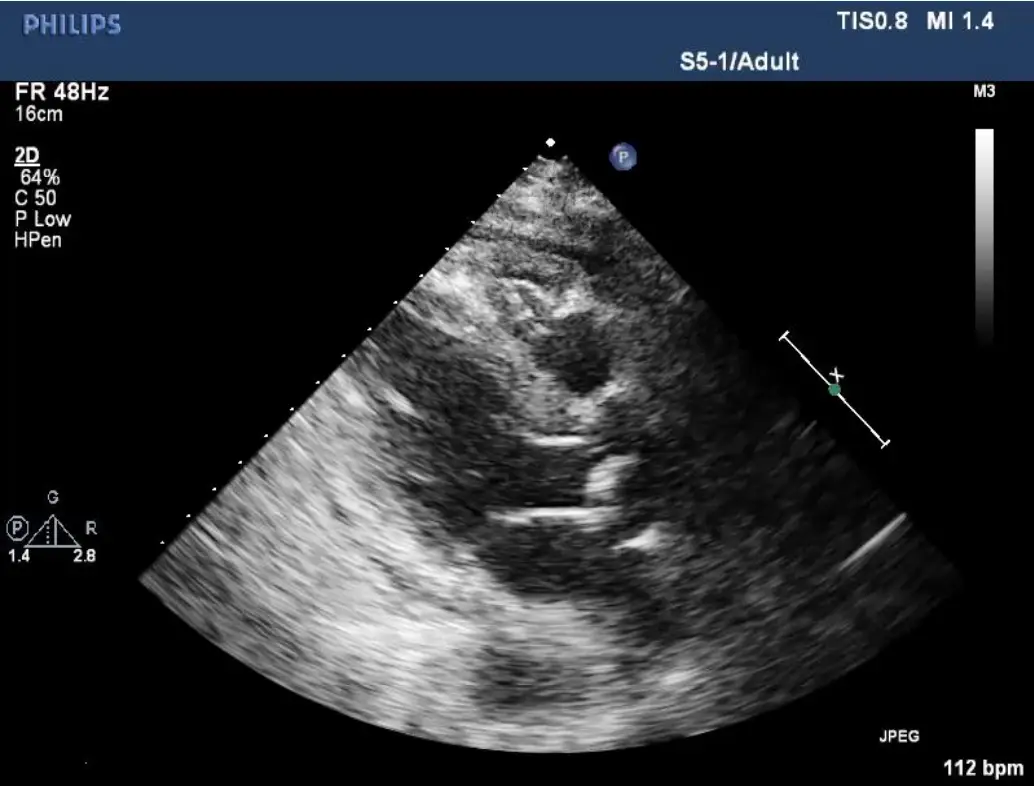

- Parasternal short-axis 超音波:心室壁均勻增厚、心包膜厚度正常。